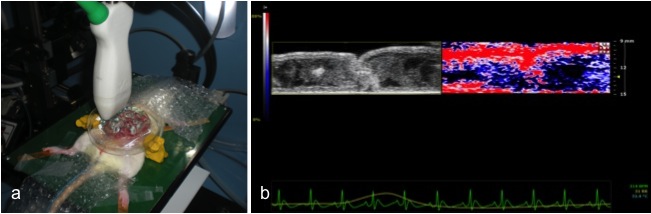

Photoacoustic imaging is an emerging modality that exploits the photoacoustic effect to combine the high contrast of optical imaging with the spatial resolution and penetration depth of ultrasound. A key feature of PA imaging methods is that they exploit optical contrast but employ US detection principles. The PA effect offers a way to take advantage of the ability of light to penetrate into the body and let us defeat light diffusion by using US waves to see the penetrating light. The main advantage of this hybrid approach is that the optical properties of biological tissue, including high contrast and spectral specificity, are encoded in an ultrasound signal. Resolutions of better than 1 mm can be obtained at depths measured in centimeters (up to 7) and not in millimeters, depending on the laser wavelength and transducer frequency used, opening up entirely new regimens of optical imaging. From a clinical standpoint, PA imaging is complementary in nature and synergetic with US and a combined US and PA imaging system can be easily implemented due to the presence of a shared detector and associated electronics. Furthermore, such a system will be readily accepted by clinicians familiar with US imaging.